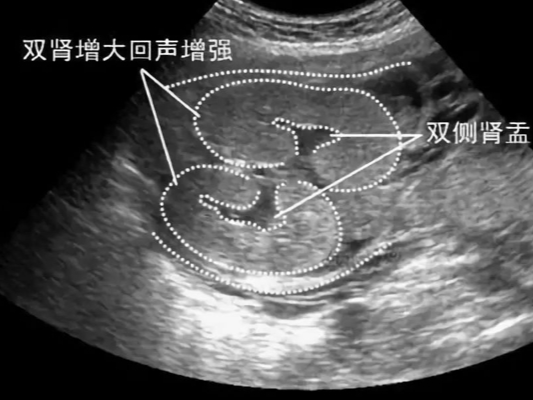

什么是肾盂?肾盂简单的说,就是肾和输尿管连接的地方。胎儿肾盂分离是由于肾结石、输尿管畸形,导致尿液无法正常排出,于是肾盂被充盈变大形成的。胎儿憋尿时,也可以发生肾盂分离。

双侧肾盂分离如图所示

国外有数据显示,发生肾盂分离的宝宝男婴占有60%,如果说双肾盂无分离可能孕妈肚子里怀的就是女宝宝。虽然说有这样的数据支持,但是这也不足以说明能够从肾盂是否分离能用来判断胎儿性别。

肾盂分离是指肾脏与输尿管连接处因先天疾病或物理因素导致尿液无法排除,肾盂被充盈胀大的情况。是一种先天性教常见的疾病或随机事件,与胎儿的性别无关,所以说,肾盂分离可能男孩也可能是女孩。